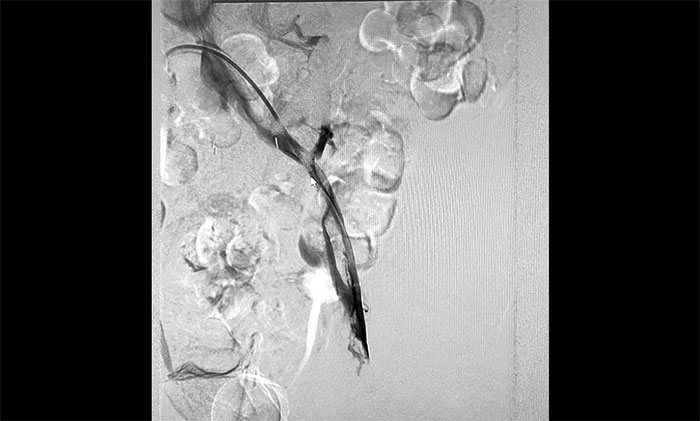

12月15日,席刚明教授在王贵平博士及介入团队协助下顺利行将一个形似伞状的人工滤器经患者右侧股静脉穿刺迅速置入肾静脉下方,“网”住了通往心血管和肺部的致命栓子,阻挡血液栓子进入肺动脉,及时挽救了患者生命。之后对病变血管进行了血栓抽吸术,及接触性溶栓,抽出了大量血栓,复查下肢造影示血栓基本消失,下肢静脉血管再通,整个手术顺利完成。术后,患者下肢肿胀好转。

▲ 下腔静脉滤器顺利置入